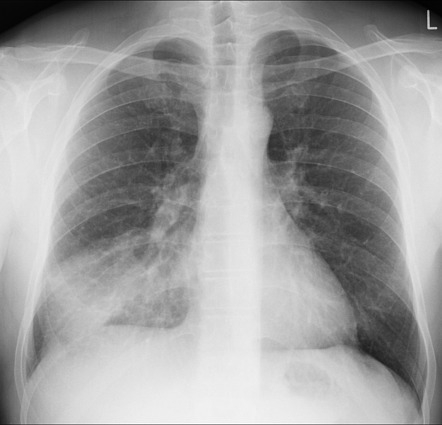

肺塌陷

77_600.jpg